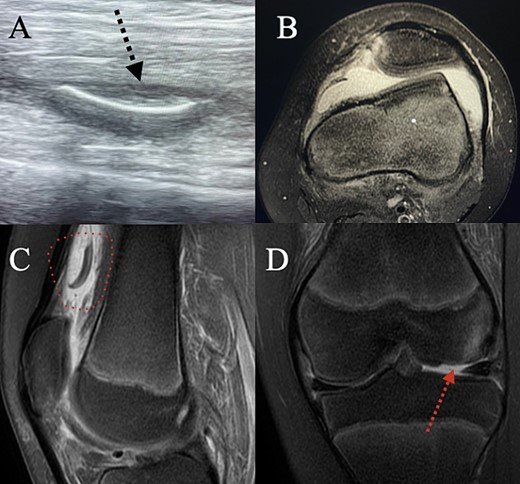

The cast was removed, and the patient underwent thorough examination. A considerable amount of knee effusion was observed, accompanied by pain localized to the lateral femoral condyle. Ultrasound evaluation of the knee joint identified a potential osteochondral fracture in the suprapatellar pouch (Fig. 2A). Subsequently, an MRI examination was promptly conducted, confirming the presence of an (osteo)chondral fragment of the lateral femoral condyle, measuring 2.4 × 1.35 cm2, subsequent to patella dislocation (Fig. 2).

(A) Ultrasound examination of the supra-patellar pouch revealed a possible chondral fragment floating there. (B) Axial MRI showing lateralization of the patella, trochlea dysplasia and a torn MPFL. (C) Sagittal MRI confirming that there is a chondral fragment in the supra-patellar pouch. (D) Coronal MRI showing the chondral fracture in the lateral femoral condyle.